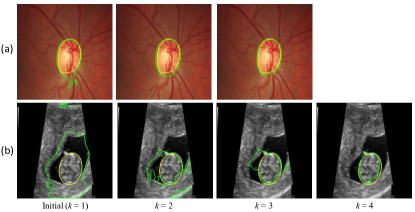

To validate our noise-robust iterative method to learn from noisy pseudo labels obtained by , we compared the following variants: 1) U-Net (baseline) that learns from the pseudo labels using a standard Dice loss without considering the existence of noise; 2) U-Net (MAE) that uses MAE loss [38] for training; 3) U-Net () that uses generalized cross entropy loss [40] for training; 4) U-Net trained with Dice loss from samples selected by our LQSS, which is referred to as U-Net (LQSS). These four methods only train the model once without iterative training, and were further compared with: 5) U-Net (LQSS + IT) that refers to U-Net (LQSS) followed by iterative training with Dice loss; and 6) U-Net (LQSS + IT + wDice) that refers to U-Net (LQSS) followed by iterative training with our noise-weighted Dice loss. For the last two variants, the round number determined by the validation set was 3 and 4 for optic disc segmentation and fetal head segmentation, respectively. The quantitative evaluation results are shown in Table 4, which shows that LQSS obtained better performance than the baseline, and using iterative training and noise-weighted Dice loss further improves the segmentation accuracy. Fig. 8 shows that our LQSS is able to reject low-quality pseudo labels with some noise, e.g., over segmentation with false positives. Note that in Fig. 8(a), the second rejected case of has a higher contrast than the first accepted case, which shows our LQSS does not tend to only select easy samples. Fig. 6 demonstrates the refinement of pseudo labels at different rounds of training stage. Fig. 9 shows the performance at different rounds of our iterative method to learn from noisy pseudo labels obtained by . It shows that the performance increased at the beginning and reached a plateau after two rounds for optic disc and three rounds for fetal head, and that noise-weighted Dice loss is better than Dice loss during the iterative training. We compared our ellipse-based shape prior with circle-based shape prior to obtain the pseudo labels, and they are denoted as U-Net (baseline) and U-Net (baseline)∘, respectively. Results in Table 4 show that modeling optic disc and fetal head as ellipses largely outperform modeling as circles.